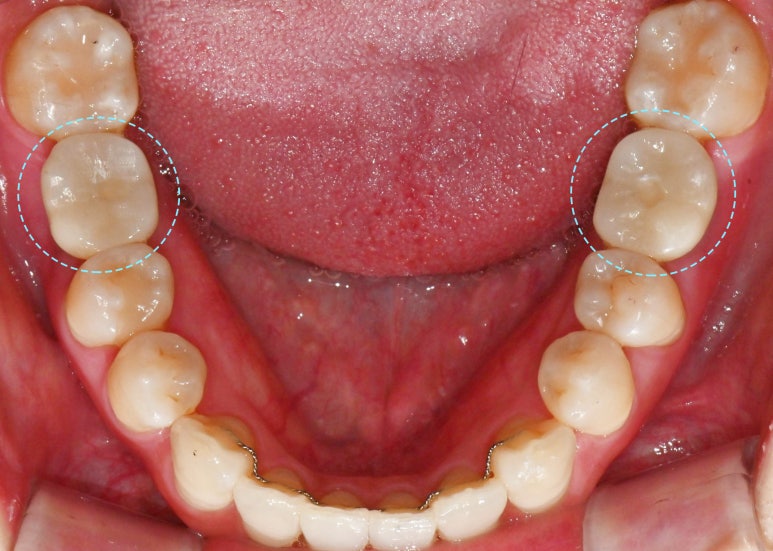

하악도 마찬가지로

사랑니가 존재하고,

여기서 주목해야 될 것은 바로

만기 잔존해 있는 치아입니다.

왼쪽 아래 부러진 채로 남아있는

유치가 있으며

오른쪽은 언제 빠졌는지는 모르나

이가 빠진 채로 시간이 지나면서

그 뒤 어금니가 앞으로 기울어져

공간이 좁아져있습니다.